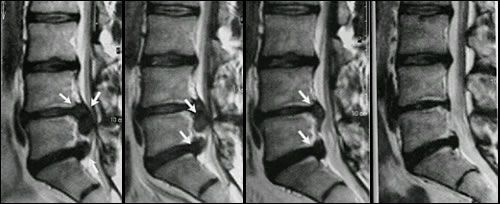

• Ernia discale, trattamento con ozonoterapia

Oggi ho conosciuto il dr Zaffaroni e diciamo che ho avuto subito una buona impressione, la sua professionalità e la terapia proposta per risolvere la mia ernia discale mi sembra convincente per cui incrocio le dita nella speranza di avere beneficio con queste sedute di ozonoterapia.

A Luglio ho trattato con Ozono una brutta ernia S1L5 che per 3 anni mi ha dato dolori continui, nell’arco di 15 giorni sono stato meglio e da agosto fino a dicembre i dolori dono spariti. Consiglio il trattamento e consiglio il dr Zaffaroni ( puntualissimo e non ho perso tempo). Oggi sono bloccato da infiammazione da Protusione, fatto trattamento e già dopo 6 ore sto molto meglio.

Mi sono trovata molto bene, il Dott. Zaffaroni è professionale e molto chiaro. Ho trovato beneficio al mio problema di discopatia alla schiena con l'ozono terapia già dalla prima seduta. Mi rammarico solo di non averla provata anni fa... È un vero peccato esserne venuta a conoscenza tardi e per puro caso.

Buongiorno devo dire che già dalla prima terapia di ozono ho sentito dei benefici e con un ernia messa male come la mia è davvero positivo